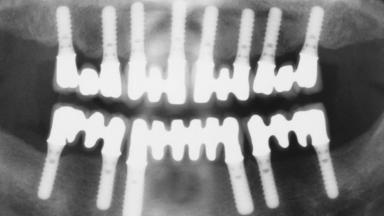

Immediate Loading of Eight Implants in the Maxilla and Six Implants in the Mandible and Final Restoration with Three-Unit and Four-Unit FDPs

# of Implants 14

Type of Implants One-Piece

Modality 6+ implants with immediate loading

Loading Protocol Immediate